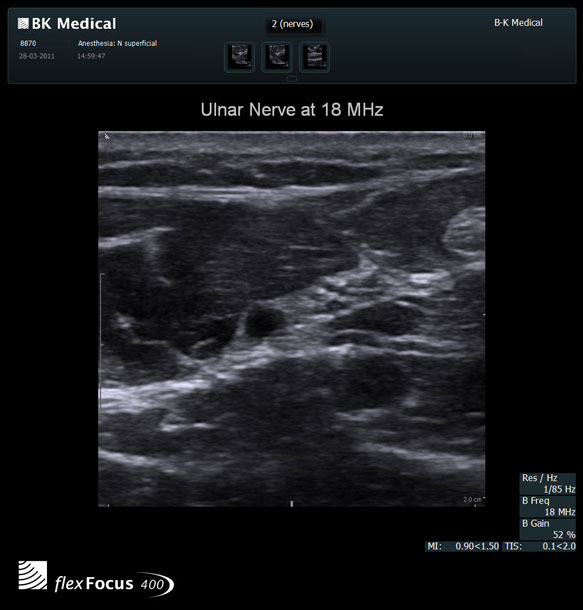

High resolution ultrasound imaging for needle-guided procedures.

The Flex Focus 400 exp ultrasound system offers premium image quality with fast frame rates for excellent temporal resolution. The system features Automatic Mode Adjustment (AMA) to optimize high resolution B-Mode Imaging when changing modes and depth.

Transducers Designed for Guidance

BK Medical offers high-frequency linear transducers, imaging from 18-2 MHz for upper and lower extremities, and curved array abdominal transducer 8820e for special deep nerves or paravertebral/spinal applications. Our transducers provide superb detail that makes it easy to see your needle during procedures.